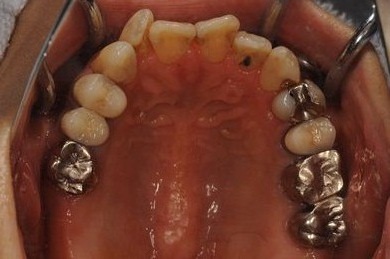

抜歯即日スピードインプラント+セラミック治療

| 性別/年齢 | 女性 / 52歳 | ||||||||||||||||||||||||||||||||

| 治療内容 | インプラント2本(抜歯即日スピードインプラント)、ハイブリッドセラミッククラウン5本(セラミック用土台2本)、ハイブリッドセラミックインレー1本 | ||||||||||||||||||||||||||||||||

| 総治療費 | 1,052,783円 | ||||||||||||||||||||||||||||||||

| 治療期間 | 1年3ヶ月 |